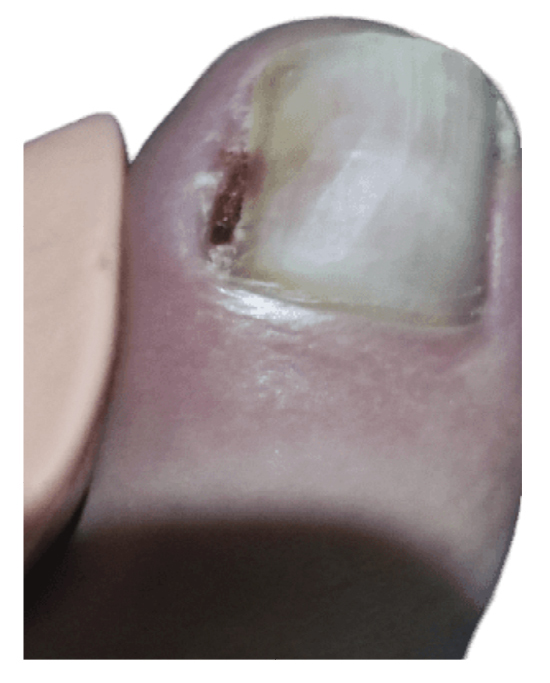

The patient initially showed improvement in pain, although it never completely subsided (Figure 4). She reported recurrence of the nail lesion, which led her to seek a second opinion 6 weeks after the intervention with another podiatrist. This latter podiatrist, on December 27th (Figure 5), performed a bacterial culture of the lesion, which turned out negative, and also evaluated the lesion by ultrasound (without report). On January 13th, the patient underwent surgery using the phenol-alcohol technique on the lateral border of the first toe of the left foot (Figure 6).

Figure 5. 16th week. Negative microbiological culture and sonograhpic assessment (not available).

Within 3 weeks after the third intervention, the patient reported recurrence of the lesion and painful symptoms (Figure 7). The patient decided to attend the traumatology department (February 2023) where an MRI (T2FS and DPFATSAT) was requested. It showed an occupying mass in the lateral third of the first toe with well-defined borders and bone involvement (Figure 8) with the following report: “At the level of the distal phalanx of the 1st toe in the nail region, there appears to be a solution of skin continuity with a heterogeneous, a dense 15 mm x 14 mm collection in the lateral region of the parapharyngeal soft tissues, remodeling the bone and coming into contact with the flexor tendon, which could be consistent with a postoperative abscess/phlegmonous collection. Some bone edema in the distal phalanx is suspected, without completely ruling out incipient osteomyelitis. To be correlated with medical history and surgical protocol performed.”

Figure 7. 21th week. Recurrence of lesion after phenol-alcohol surgery.